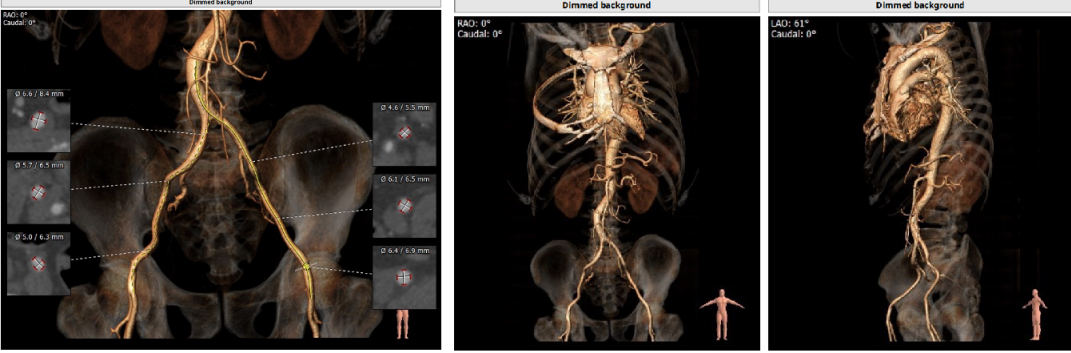

type0型二叶瓣,中度钙化

Annulus:27mm

LVOT:31.7mm

STJ:33.6mm

升主动脉:37mm

LM:19.3mm

RM:22.5mm

CT分析

Anulus 27,LVOT 34.2,短径25.9,STJ高度可,初步预估32/29瓣膜。

窦部短径26mm、左右冠空间足够,冠脉高度可心脏角度51°、升主未增宽。

体位:LAO 4° CRA 7° ;type0型二叶瓣一个角度即可,有需要可测cusp-overlap角度;轻度钙化,位于瓣叶游离缘,基本不影响瓣膜位置。

心尖薄,导丝塑性需注意形态,入路可,右股做为主入路。

预装32瓣膜,25球囊扩

功能型二叶瓣,轻度钙化、瓣叶增厚

Annulus25.7mm

LVOT:24.0mm

STJ:32.2mm

升主动脉:35.9mm

LM:13.2mm

RM:16.1mm

Anulus 25.7、LVOT 23.7;STJ高度可,窦部空间足够;初步预估29/32瓣膜。

升主未见增宽,角度尚可,轻度钙化。

左右冠高度不低,球扩体位:LAO 26、CRA 18;释放体位:LAO 9、CRA 4;心室腔略小。

入路直径足够,分叉点足够高。右股作为主入路。